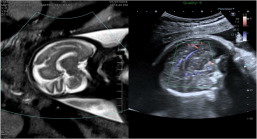

6. 智能融合&智能导航技术(Smart Fusion&Smart Navigation):智能融合技术可实现先前检查所获取的超声容积数据与实时2D超声图像之间的自动位置匹配,可用于介入治疗评估;也有CIVCO omniTRAX装置,实现超声图像和CT/MRI图像之间的自动位置匹配。

智能导航:利使用装有传感器的穿刺针,在超声图像上叠加穿刺针导航引导线,模拟显示穿刺针的路径和针尖的位置来实现导航,实时双屏幕针道显示,临床上利于穿刺介入。